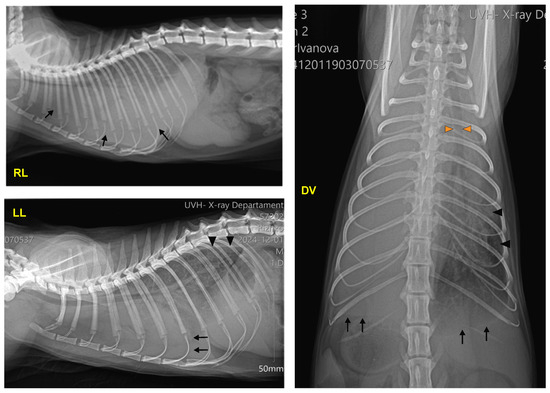

On control lateral radiographs (Figure 6), the cardiac silhouette was already clearly seen. Confined dense focal uniform shadows (atelectasis) were observed in the caudodorsal part of the lungs. The dorsoventral view demonstrated a uniform radiopacity in the area of the costophrenic angle, with retraction of the lung lobe (on the left side). The trachea was not displaced, the heart was visible, and moderate atelectasis was present.

Figure 6. Right lateral (RL), left lateral (LL), and dorsoventral (DV) radiographs of the patient during the control examination 15 days after the end of antifungal therapy: areas of moderate atelectasis (arrowheads on RL and LL views); uniform radiopacity in the area of the costophrenic angle (black arrows; DV view).